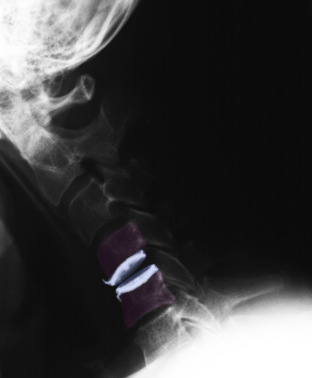

Πρόσθια αυχενική δισκεκτομή και τοποθέτηση τεχνητού αυχενικού δίσκου (μπλέ) Α6-Α7. Ακτινογραφίες με τον αυχένα σε ουδέτερη θέση (αριστερά), έκταση (κέντρο) και κάμψη (δεξιά). Αναδεικνύεται η κίνηση στο χειρουργημένο μεσοσπονδύλιο διάστημα. |